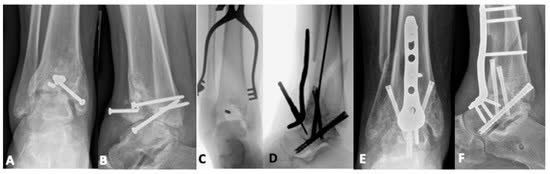

Этапный протокол (золотой стандарт)

Этапное лечение (протокол Sirkin) остаётся золотым стандартом при переломах пилона с повреждением мягких тканей.

Этап 1 (день 0–1):

- Временная чрескостная фиксация аппаратом внешней фиксации (АВФ) — дельта-рама или блокирующая конструкция через голеностопный сустав (возможно также использование классических конструкций)

- Репозиция малоберцовой кости и остеосинтез

- Обработка раны при открытом переломе

- Опционально: ограниченная репозиция и фиксация большеберцовой кости (LTRF — Limited Tibial Reduction and Fixation) при первичной операции

Этап 2 (день 10–21, при адекватном состоянии мягких тканей):

- Окончательный остеосинтез через соответствующий доступ на основании данных КТ

- Тест «морщин» (wrinkle test) — появление складок кожи свидетельствует о готовности мягких тканей к операции

Сроки: среднее время между этапами при стандартном протоколе 15,61 ± 8,59 дней. При выполнении LTRF на первом этапе время сокращается до 10,86 ± 7,44 дней (на 4,75 дня быстрее, P=0,009), а продолжительность окончательной операции уменьшается на 98 минут (P<0,001) без увеличения частоты инфекции (3,1% vs 2,5%, P=0,86) [Hreha et al., Foot Ankle Int, 2022].

Этапный протокол при переломах C3

Gao et al. (J Pers Med, 2023) предлагают модифицированный двухэтапный протокол:

- Этап 1: фиксация малоберцовой кости + задней колонны + АВФ

- Этап 2: фиксация медиальной и передней колонн

Раннее восстановление задней колонны позволяет вернуть конгруэнтность суставной поверхности и улучшить условия для окончательного остеосинтеза.

Хирургические доступы

Переднелатеральный доступ

- Показания: переднелатеральный фрагмент (Chaput/Tillaux-Chaput), переднелатеральная колонна

- Разрез между сухожилиями длинного разгибателя пальцев и латеральной лодыжкой

- Переднелатеральный фрагмент присутствует при большинстве переломов с вовлечением суставной поверхности дистального отдела большеберцовой кости [Rammelt et al., JBJS Am, 2022]

Заднелатеральный доступ (положение на животе)

- Показания: задняя колонна (фрагмент Volkmann), заднелатеральный вариант пилона

- Между сухожилиями малоберцовых мышц и длинного сгибателя первого пальца

- Позволяет напрямую визуализировать заднюю суставную поверхность

- Комбинация заднелатерального и заднемедиального доступов: частота раневых осложнений 6%, репозиция <1 мм ступеньки/щели в 94% случаев [Campbell et al., J Orthop Trauma, 2022]

Принципы фиксации

Фрагмент-специфическая фиксация по колоннам

Принцип колонного остеосинтеза: каждая повреждённая колонна фиксируется индивидуально через оптимальный для неё доступ. При переломах типа С необходима стабилизация минимум двух колонн (для четырёхколонной теории); фиксация всех повреждённых колонн не всегда обязательна — стабилизация 2–3 ключевых колонн может быть достаточной [Bakan et al., Injury, 2023].

Медиальная колонна — ключевая для механической стабильности. Варианты фиксации: опорная (buttress) пластина по медиальной поверхности, одна треть трубчатая пластина или винты. Одна треть трубчатая пластина обеспечивает более раннюю осевую нагрузку и меньшую потерю репозиции по сравнению с изолированными винтами [Wang et al., Ann Transl Med, 2022]. Стабилизация медиальной колонны + как минимум одной дополнительной колонны — минимальный объём при сложных переломах [Bastias & Lagos, 2020].

Передняя колонна (переднелатеральная) — фиксация дистальной Т-образной или L-образной опорной пластиной. Пластина устанавливается как buttress по передней поверхности, предотвращая вторичное смещение переднего фрагмента (Chaput/Tillaux-Chaput). Переднелатеральный фрагмент присутствует при большинстве переломов пилона с вовлечением суставной поверхности [Rammelt et al., JBJS Am, 2022].

Средняя (центральная) колонна — зона импакции суставной поверхности (die-punch). Фиксация через заднемедиальный доступ. Техника: подъём импактированного суставного фрагмента, заполнение дефекта аутокостью или костным заменителем, фиксация субхондральными винтами и/или опорной пластиной. Ступенька суставной поверхности ≥2 мм достоверно ухудшает исходы [Gao et al., 2023].

Заднелатеральная колонна (задняя лодыжка / фрагмент Volkmann) — задняя антискользящая (antiglide) пластина через заднелатеральный доступ. Одномоментная фиксация с малоберцовой костью через тот же доступ экономит время и снижает хирургическую агрессию. Задняя колонна повреждается в 88% случаев — это наиболее часто вовлекаемая колонна [Lou et al., Injury, 2023].

Латеральная колонна (малоберцовая кость) — опорная или мостовидная пластина. Показания к фиксации: использование малоберцовой кости как инструмента непрямой репозиции, повреждение синдесмоза, латеральная нестабильность.

Роль малоберцовой кости

Восстановление длины и оси малоберцовой кости на первом этапе позволяет избежать трудностей при последующих этапах остеосинтеза. Некорректный остеосинтез (чаще всего с укорочением) приведёт к синтезу дистального отдела большеберцовой кости в вальгусном положении.

Показания к фиксации малоберцовой кости:

- Малоберцовая кость как инструмент непрямой репозиции — восстановление длины и ротации конечности (наиболее частое показание)

- Повреждение дистального межберцового синдесмоза, требующее стабилизации

- Сегментарный перелом малоберцовой кости — маркер тяжёлого повреждения синдесмоза и худших исходов [Purcell et al., 2022]

Фиксация может быть отложена когда:

- Дополнительный латеральный доступ увеличивает риск повреждения мягких тканей (узкий кожный мостик между медиальным и латеральным разрезами)

- Перелом малоберцовой кости на уровне диафиза без нестабильности синдесмоза